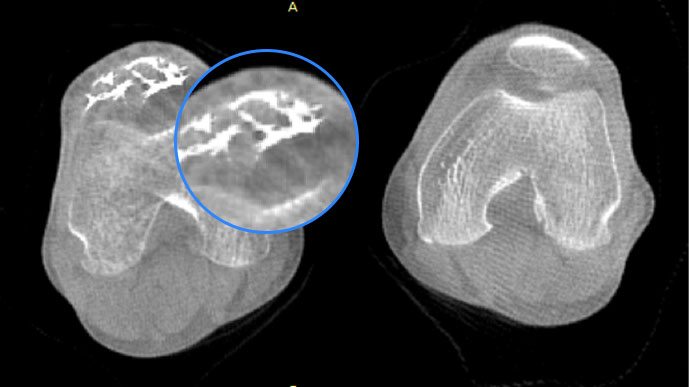

关闭金属伪影校正

开启金属伪影校正